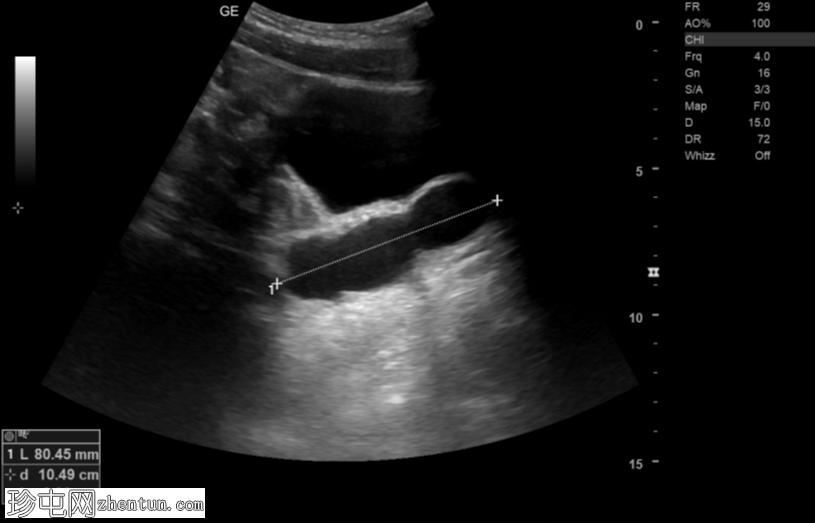

超声

左肾发育不全。

左侧精囊囊肿。